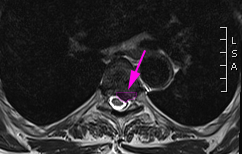

Κήλη θωρακικού μεσοσπονδύλιου δίσκου με πίεση στην τελική μοίρα του νωτιαίου μυελoύ